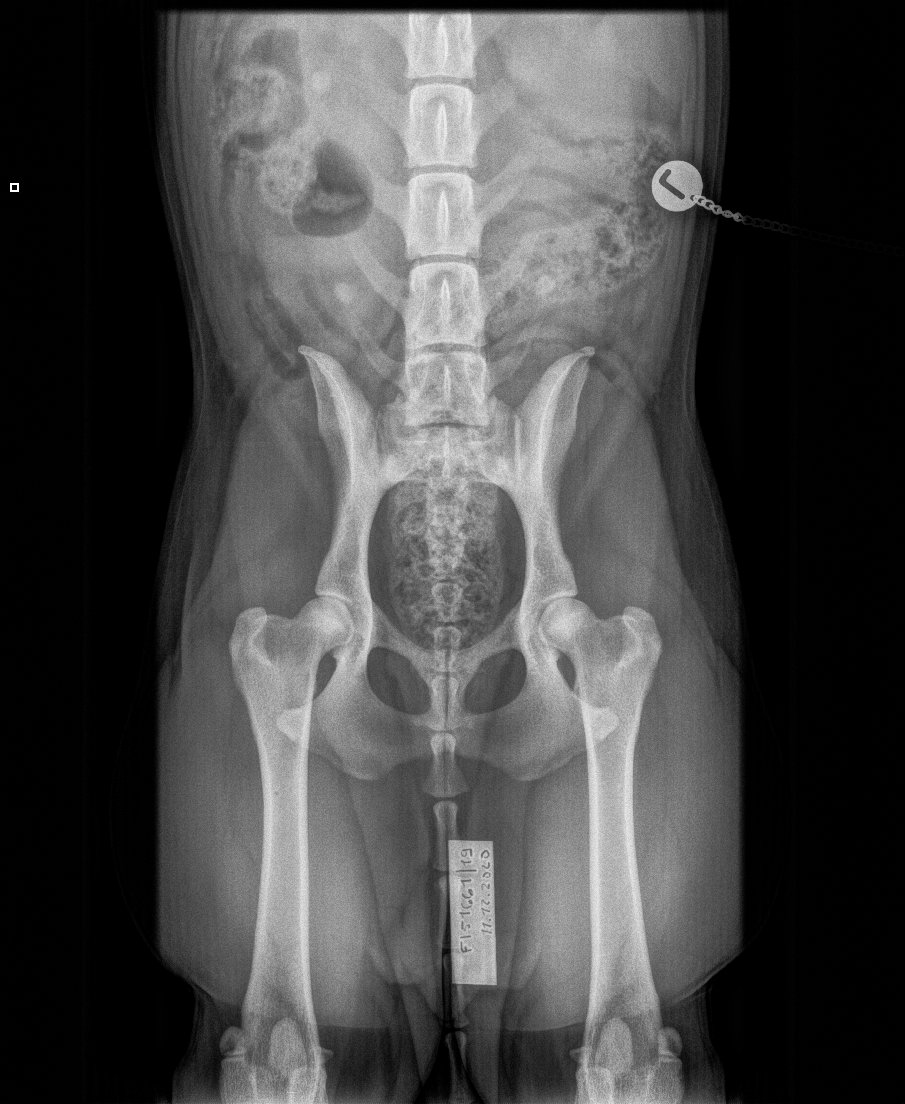

» HD A/A » ED 0/0 » silmät OK » Selkä LTV0 » Polvet 0/0